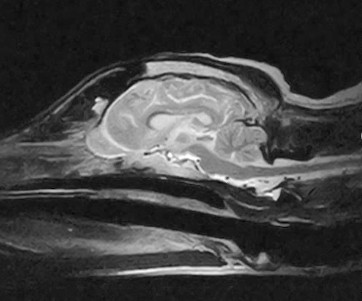

W obrębie mózgowia i trzewioczaszki najczęstszymi wskazaniami do badania MRI są:

• proces nowotworowy

• wodogłowie

• ziarniakowe zapaleniu mózgu i opon mózgowych

• diagnostyka zmian udarowych

• wstępna diagnostyka tętniaków i malformacji naczyniowych

• wstępna diagnoza gruczołu przysadki